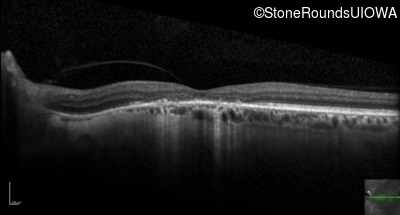

Optical Coherence Tomography - Right - 20/125 -2

Exemplar / OCT Stack

OCT Stack